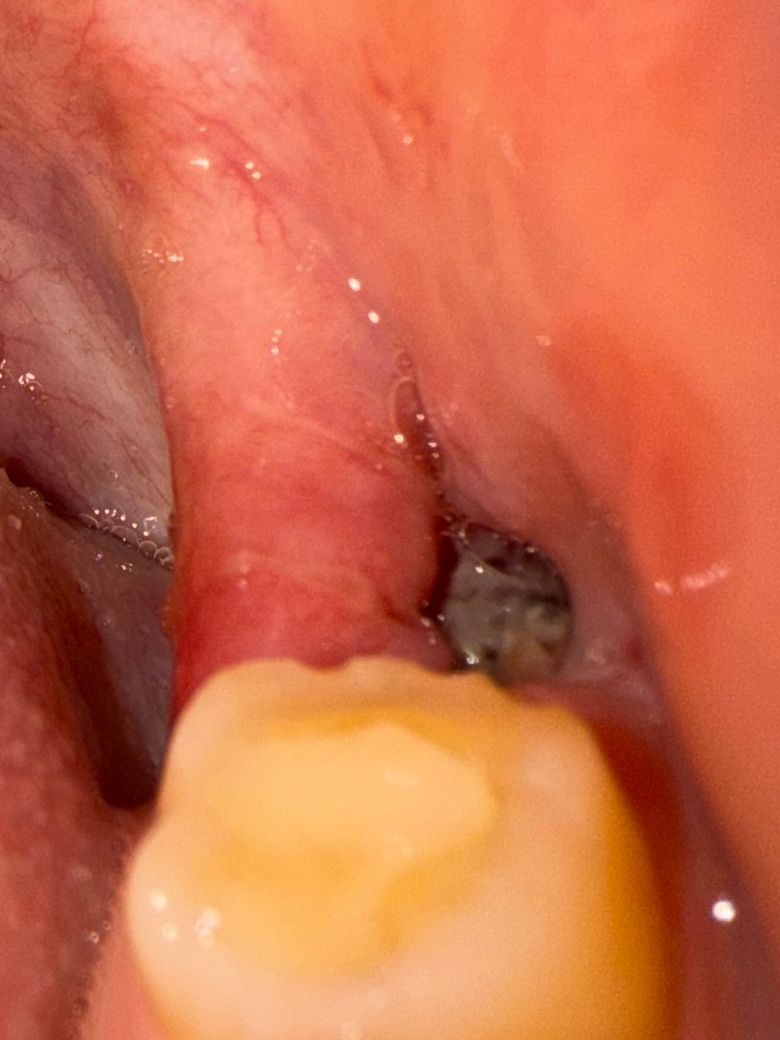

사랑니 실밥 제거 후 회색?이물질 뭔가요?ㅜㅜ

작은 구멍에 사진과 같은 회색? 이물질 같은게 있어요 ㅜㅜ 후레시로 보면 회색인데 약간 여러가지 색상이 섞인듯해요

1. 음식물인가요 ?? 혈병인가요?? 아니면 염증인가요?(드라이소켓)

물 주사기로 빼볼려고 하는데 물줄기가 약해서 그런지 안빠져요ㅠㅠ 이제 피는 거의 안나는것 같고 잇몸은 욱신욱신거리긴 해서 너무 걱정이네요

**사진주의하세요, 피가 고여있진 않아요!

상피세포 조직 등이 섞여있는 것으로 정상적입니다. 음식물도 양쪽으로 씹어서 드셔도 됩니다.

사랑니 발치를 하고나서 잇몸이 치유되는 과정중에 생기는 자연스러운 현상이니 너무 걱정하지마세요.

회복과정에서 생기는 염증, 육아조직입니다 그게 덤차 잇몸 살,뼈가됩니다

사진상에서 보이는 것은 음식물은 아니기 때문에 걱정하지 않으셔도 되고 해당 부분은 치유과정에서 생성되는 조직들이므로 무리해서 제거하시면 안되고 저 위에 침착되는 음식물만 제거해주시면 되겠습니다.